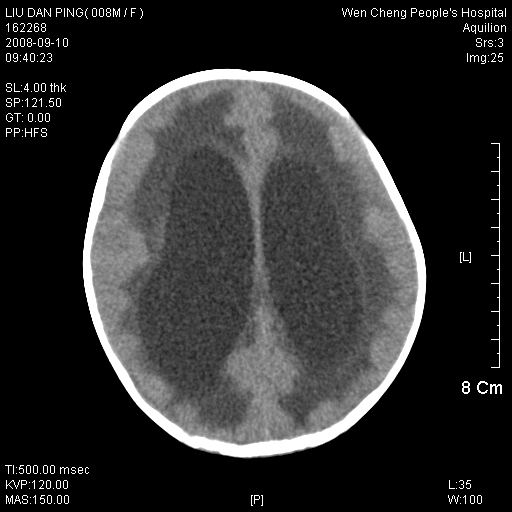

以下是引用卜一在2008-9-10 16:21:00的发言:[br]髓母细胞瘤伴梗阻性脑积水!支持![br]髓母细胞瘤特点:—般直径大于3.5cm,位于后颅凹中线之小脑蚓部。累及上蚓部的肿瘤延伸到小脑幕切迹之上,ct平扫肿瘤多呈均匀一致的高或等密度病灶,增强检查呈均匀一致的强化。病灶中有小坏死时,平扫亦可呈不均匀之混杂密度,注药后有增强。[br]

以下是引用zjzjr在2008-9-10 15:09:00的发言:[br]髓母细胞瘤伴梗阻性脑积水.